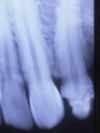

What can be seen in the following image?

A

cementoblastoma